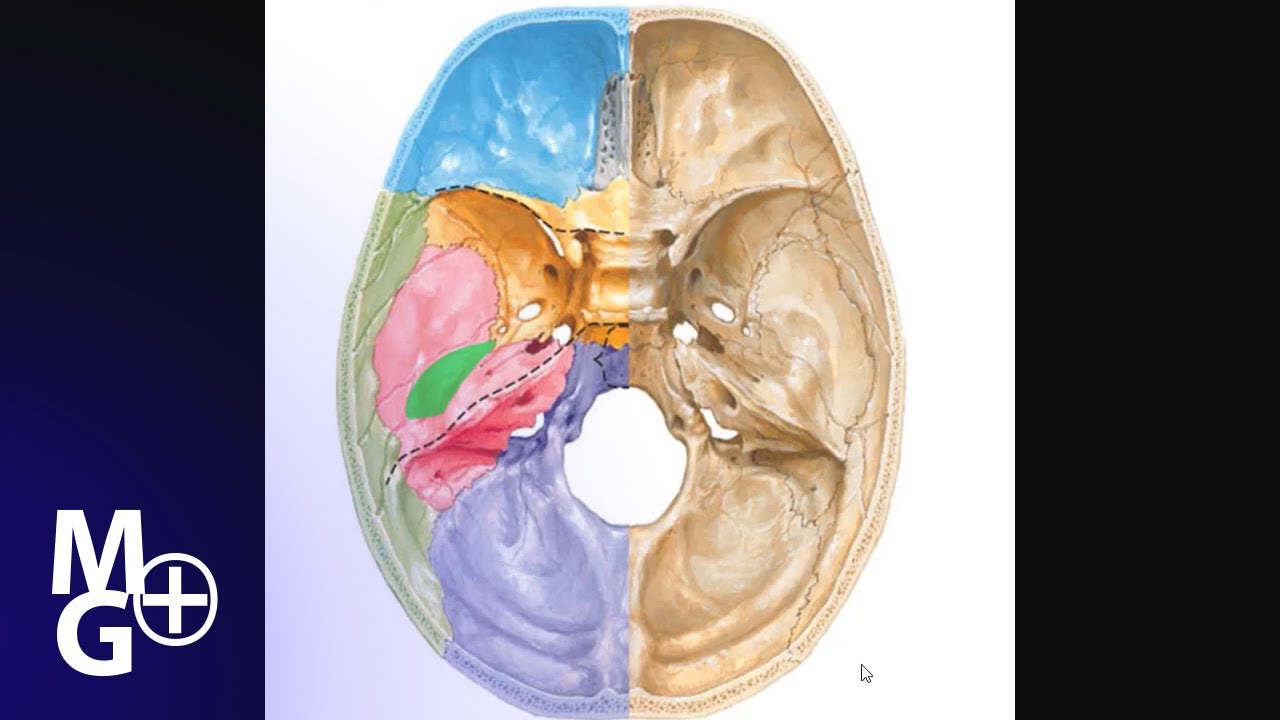

Анатомические детали: Фотографии топографии черепа с нижнего вида

Раздел: Альбом идей